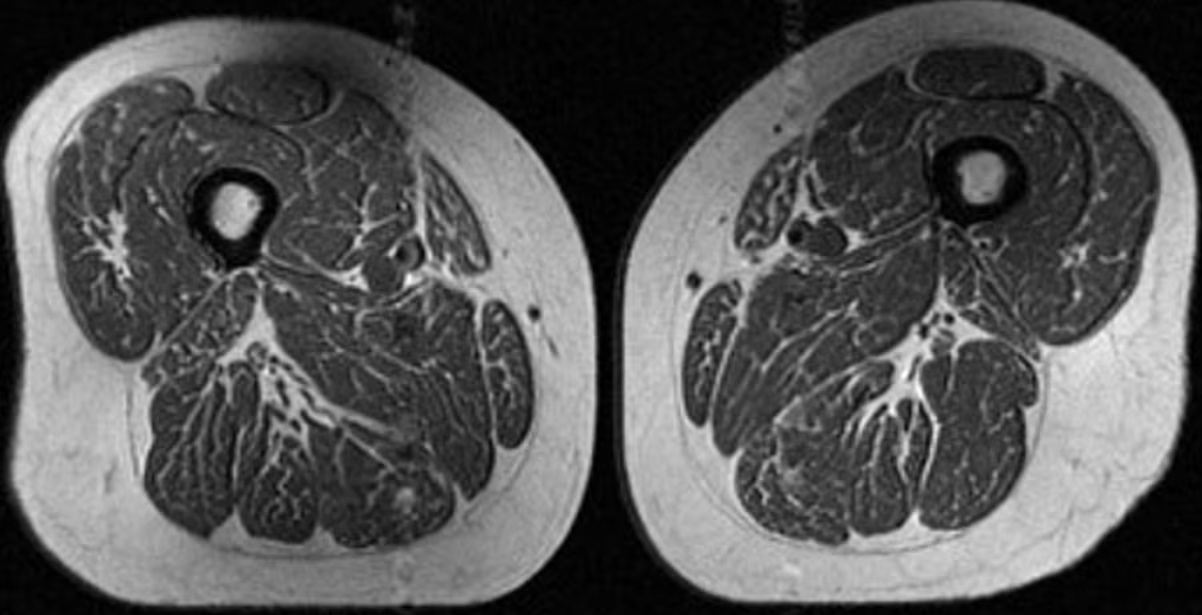

Προειδοποίηση επιστημόνων για τα υπερεπεξεργασμένα τρόφιμα: Η μαγνητική γυναίκας με τους μηρούς-μπριζόλα και ο «σιωπηλός» κίνδυνος - Το Γεγονός